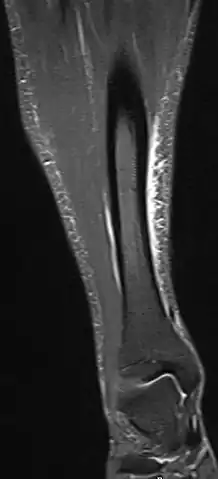

Other potential causes include stress fractures, compartment syndrome, nerve entrapment, and popliteal artery entrapment syndrome.[16] If the cause is unclear, medical imaging such as a bone scan or magnetic resonance imaging (MRI) may be performed.[3] Bone scans and MRI can differentiate between stress fractures and shin splints.[11]